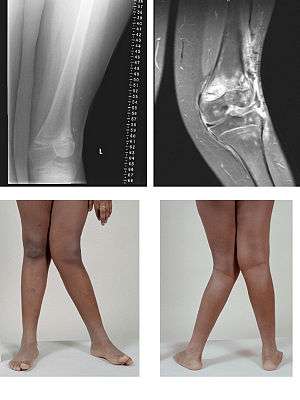

Genu valgum, commonly called "knock-knee", is a condition in which the knees angle in and touch one another when the legs are straightened. Individuals with severe valgus deformities are typically unable to touch their feet together while simultaneously straightening the legs. The term originates from the Latin genu, "knee", and valgus which actually means bent outwards, but in this case, it is used to describe the distal portion of the knee joint which bends outwards and thus the proximal portion seems to be bent inwards. For citation and more information on uses of the words Valgus and Varus, please visit the internal link to -varus.

Mild genu valgum is diagnosed when a person standing upright with the feet touching also shows the knees touching. It can be seen in children from ages 2 to 5, and is often corrected naturally as children grow. However, the condition may continue or worsen with age, particularly when it is the result of a disease, such as rickets or obesity. Idiopathic genu valgum is a form that is either congenital or has no known cause.